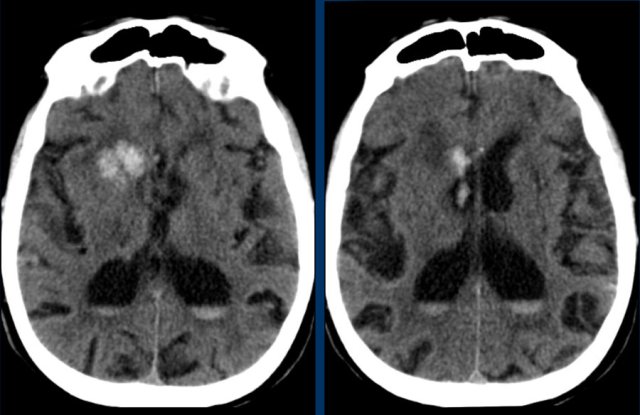

These small hemorrhages are also called microbleeds.

Notice how numerous these small hemorrhages are and primarily located in the perifery of the brain.

Hypertensive intracranial haemorrhage together with CAA make up 80% of the causes of intraparenchymal hematomas.

Think of CAA if you see multiple peripheral or lobar haemorrhages in an elderly patient.